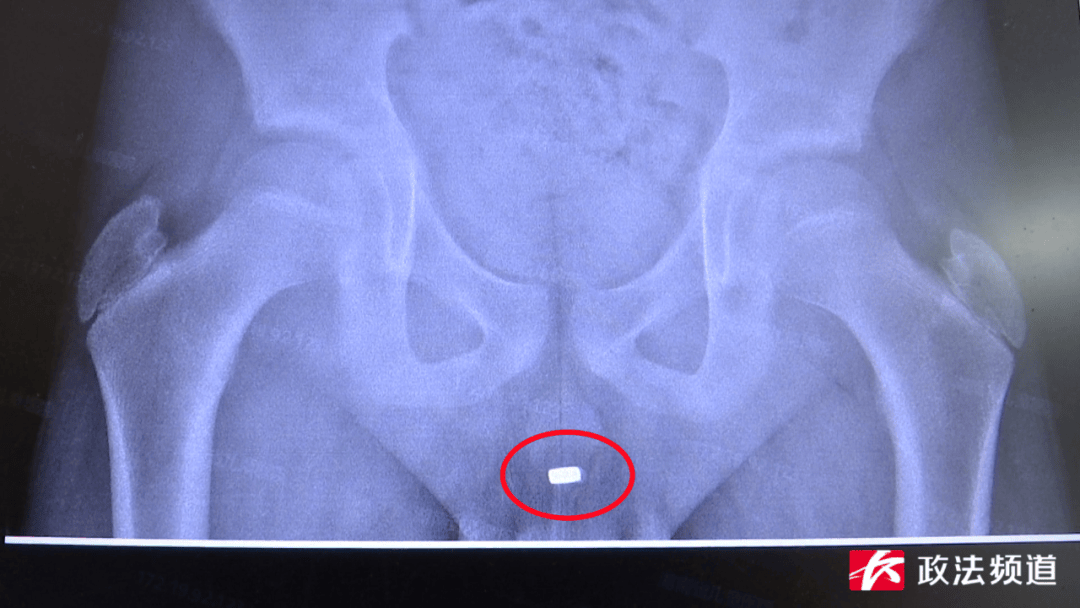

一枚玩具小金币竟然在男孩尿道两个月后才被取出。近日,湖南省儿童医院泌尿外科接诊了一名12岁的男孩童童(化名),他因青春期对身体的好奇,暑假时将玩具“火影小金币”塞入尿道。出现尿痛、血尿症状后仍不敢告知家长,直至下腹剧烈疼痛、无法排尿才被父母送至医院。

湖南省儿童医院泌尿外科接诊后,考虑到异物为金属材质,且存留时间过长可能对身体造成特殊伤害,涂磊教授团队经过严密细致的讨论与准备,在全身麻醉下为童童实施膀胱镜尿道膀胱镜检+尿道异物取出术,一枚完整的“金币”被顺利取出。

从童童体内取出的“金币”

该院泌尿外科副主任医师涂磊介绍,男性尿道长而细,存在2个生理弯曲及3个尿道狭窄处,异物进入后极易嵌顿,难以自行排出。及时取出膀胱尿道异物至关重要,若拖延至引发并发症后再治疗,会大幅增加诊疗难度。童童因为异物留滞2个多月时间,金属周围都长满了小结石,不仅造成尿道、膀胱局部损伤,也引发了童童的尿痛、尿急、血尿、排尿困难等症状,术后还需要一段时间的康复治疗。